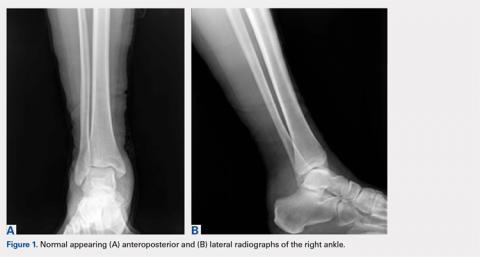

Review of her plain radiographs demonstrated no bony abnormalities, fractures, nor visible deformity (Figures 1A, 1B).